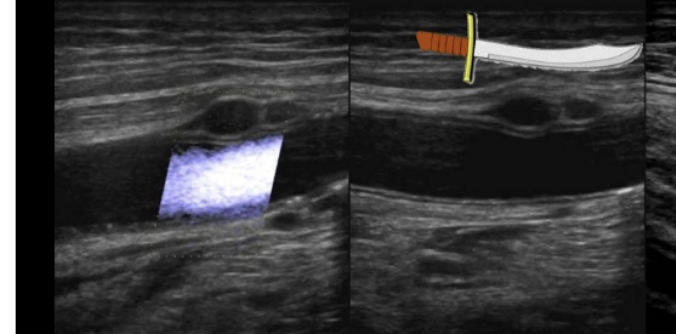

when thrombin is injected into a pseudoaneurysm, the needle puncture site should be located

.

a) as far from neck as possible

b) within 5mm of neck

c) lateral aspect of groin

d) within 1cm of neck